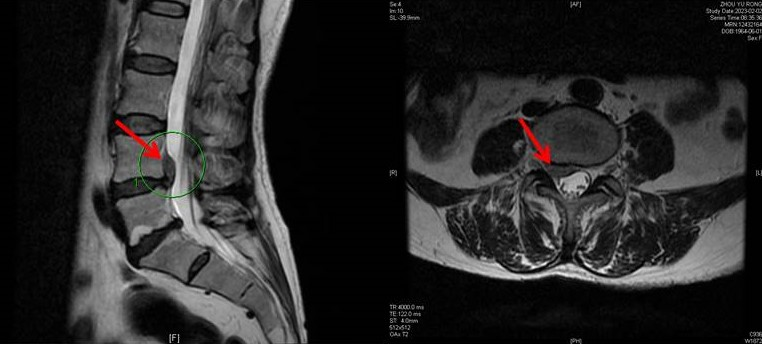

入院后,骨与关节康复科医护团队对周阿姨的病情进行了全面评估,进一步完善了磁共振检查。结果发现周阿姨腰4/腰5椎间盘有较大脱出,并向上游离,压迫神经。

考虑到周阿姨脱出椎间盘较大,如果继续保守治疗,可能肢体麻木、无力进行性加重,压迫时间过长,神经将产生不可逆损伤。骨与关节康复科医护团队经过讨论,最终决定为周阿姨进行微创手术。整个手术在局部麻醉下进行,切口仅0.8cm。术中厉驹副主任医师有条不紊的进行手术操作,并时不时和周阿姨聊天,缓解周阿姨的紧张情绪。

术中发现,由于突出髓核的压迫,神经根已经明显缺血,肿胀发白。厉驹副主任医师谨慎保护神经,顺利取出脱出的巨大髓核。椎间孔镜下观察到,在压迫解除后,神经根立刻充血变红,而周阿姨也感觉自己的右腿如释重负。